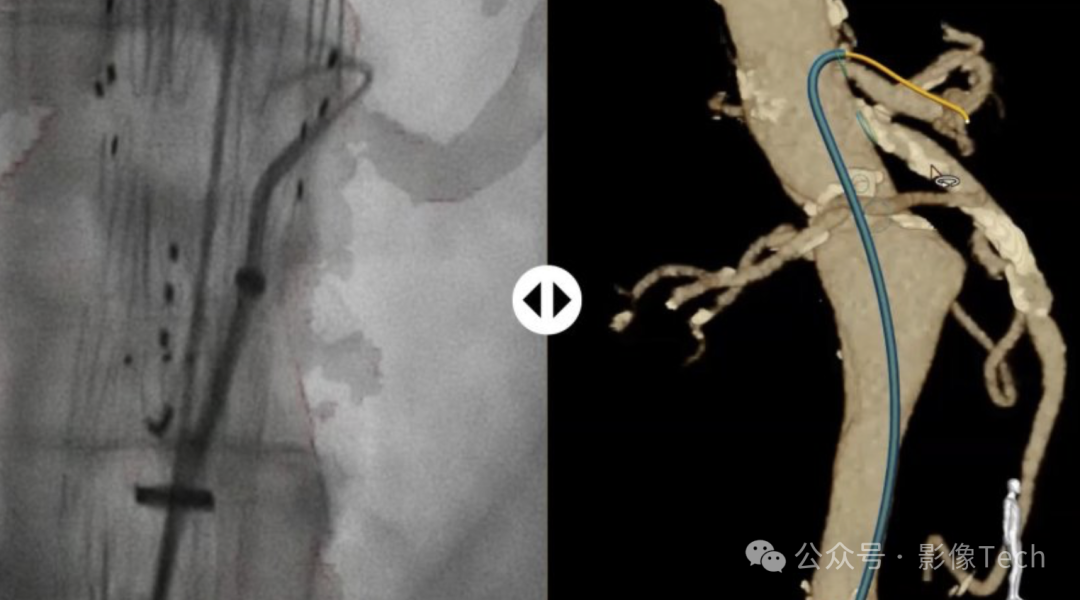

这项名为LumiGuide的技术,由Fiber Optic RealShape (FORS) 技术驱动,使得医生可以使用光来导航血管,而非X射线,被形象地称为“由光驱动的3D人体GPS”,实现了介入设备在体内的实时3D可视化,不同于传统的X射线,FORS技术使用光脉冲,显著减少了患者和医生的辐射暴露,有希望为影像行业带来新一轮的变革。

利用FOR技术的导丝集成了极细的光纤,通过发射光脉冲并分析反射信号,可在不同的成像系统(如CT扫描和X射线)上重建和可视化设备形状。

LumiGuide通过在导丝内的光纤中反射光来生成3D高分辨率彩色图像,实时从任何角度和多个视角显示病人体内的器械,包括现成的导管。这意味着医生知道自己的设备朝向哪个方向,并且能够看到他们需要前进的路径。所有这些导航都无需X射线。